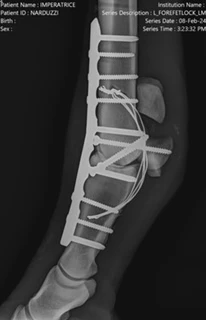

- Advanced osteosynthesis